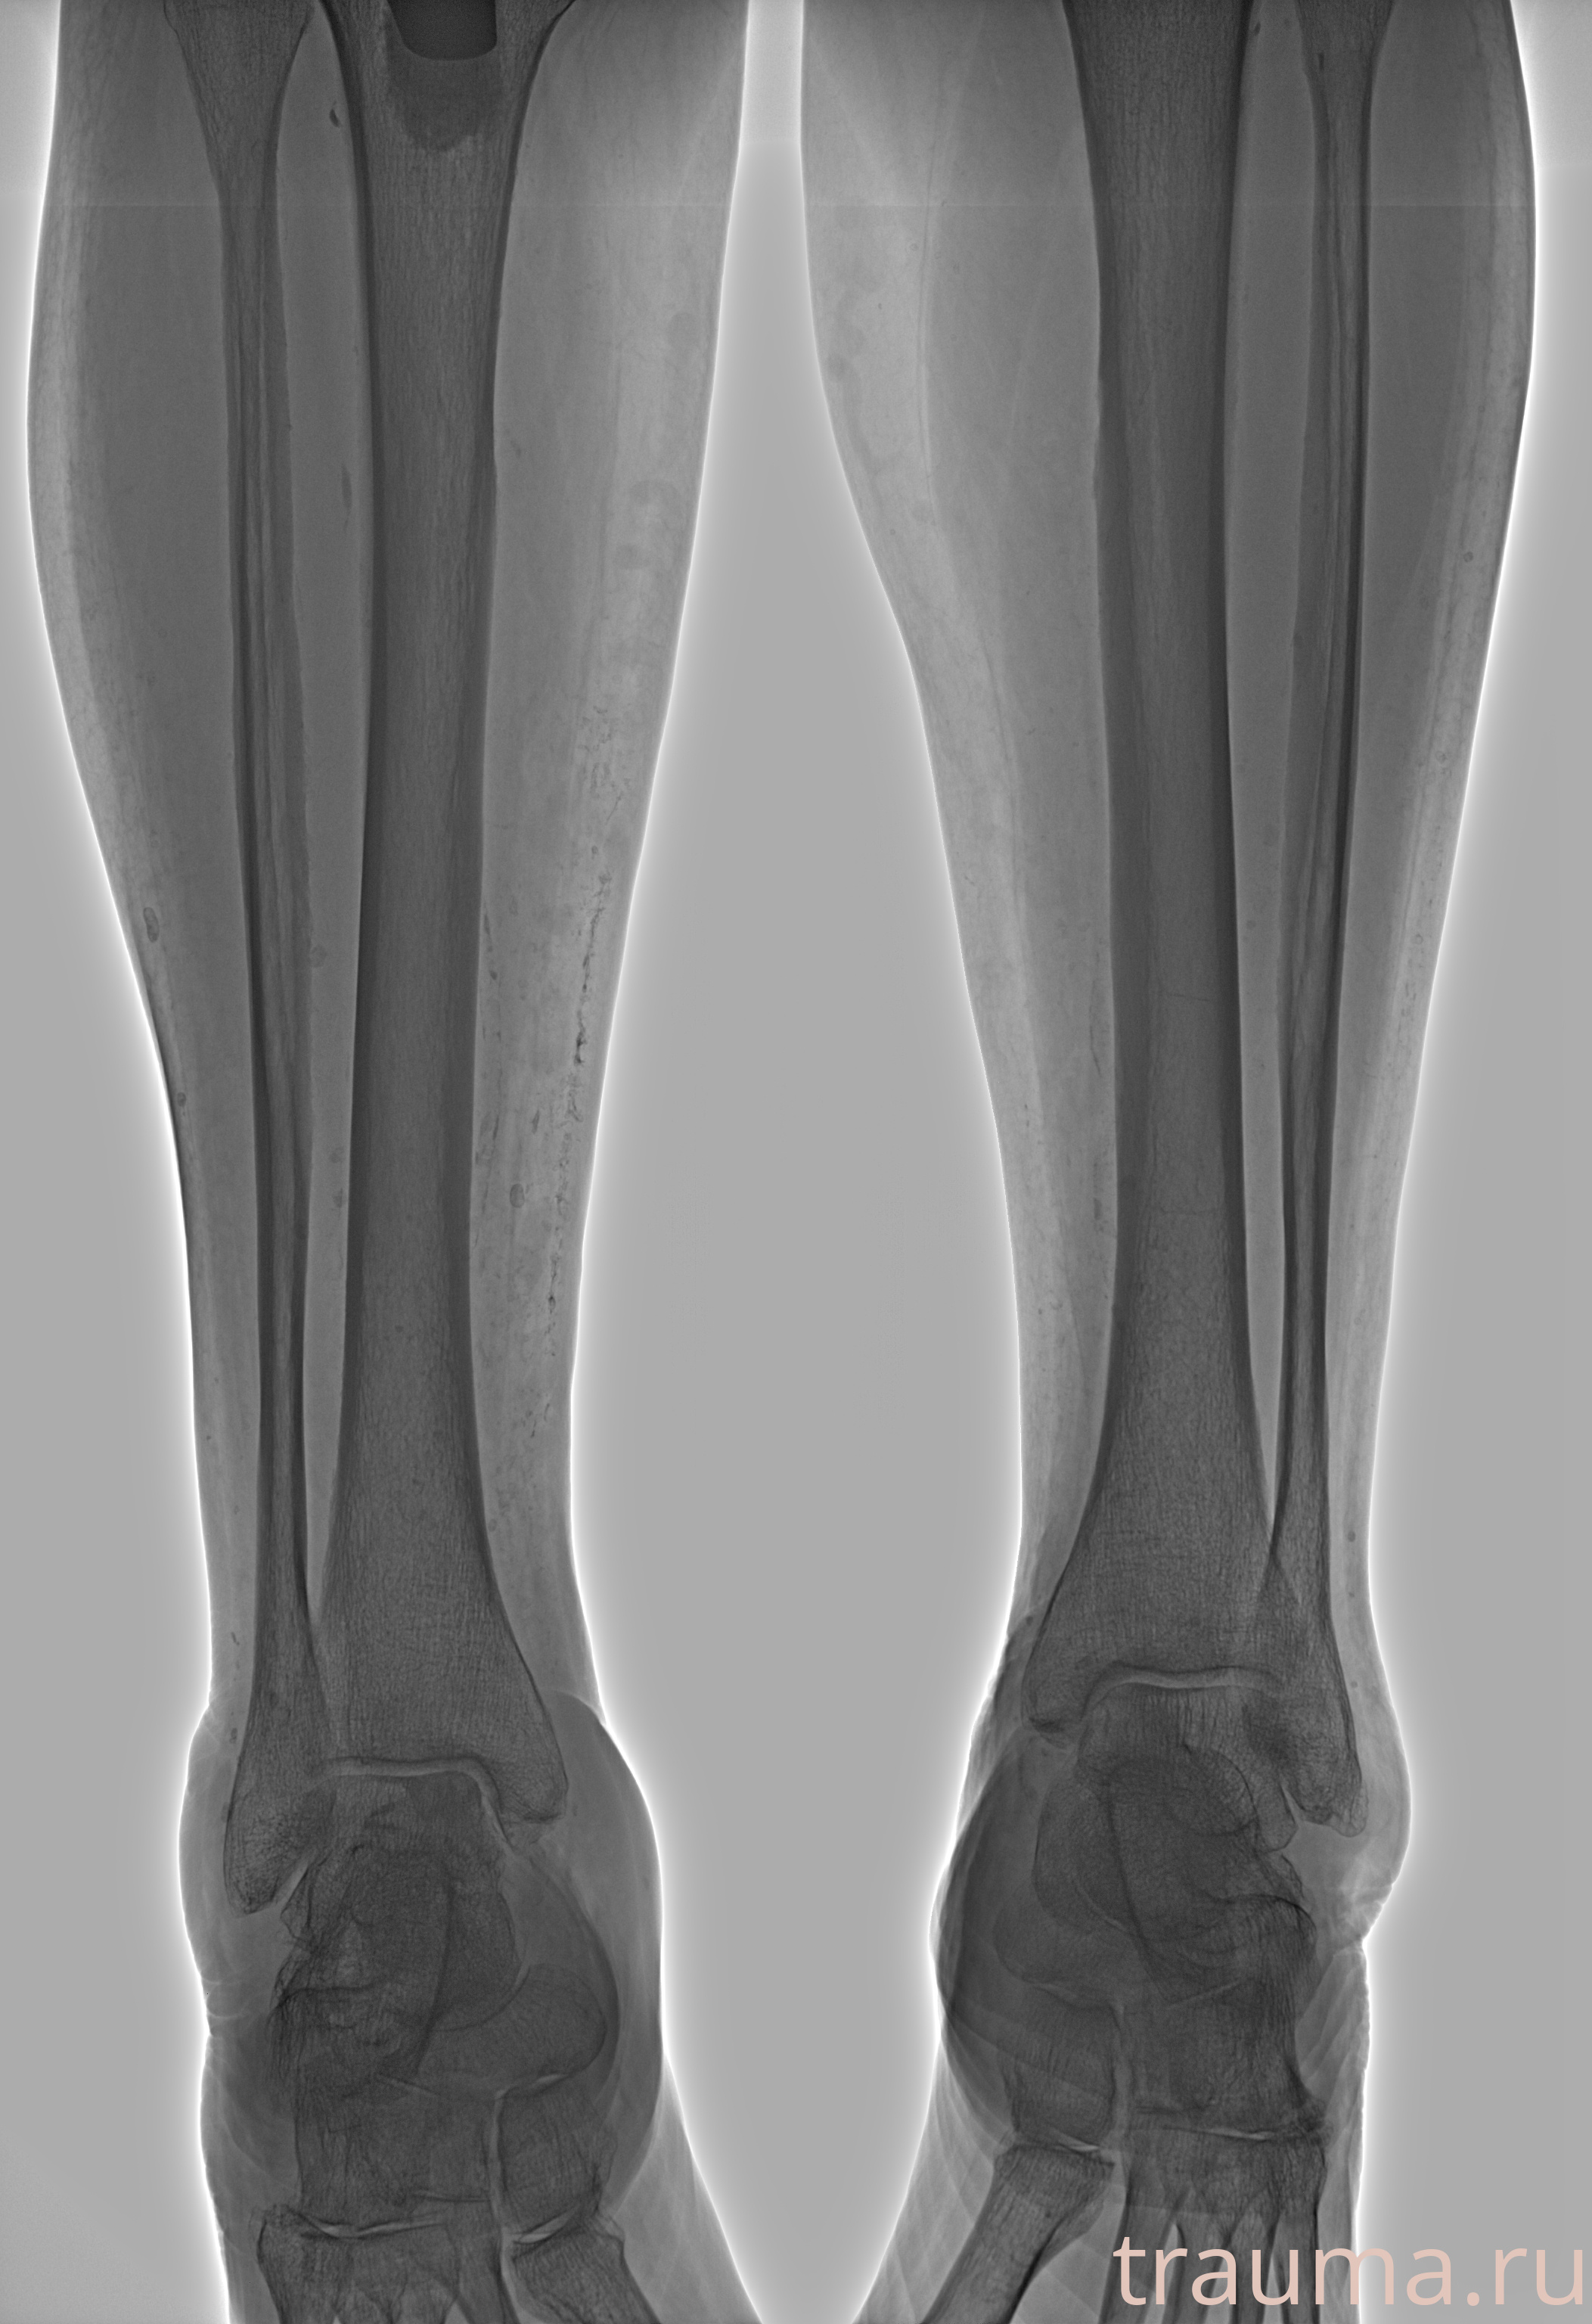

Рентген на дому: по вашему адресу приезжает врач-рентгенолог, травматолог-ортопед с мобильным рентгеновским аппаратом, проводит диагностику травмы или заболевания, делает необходимые рентгенограммы, дает рекомендации по дальнейшему лечению. Получить качественные снимки в домашних условиях возможно благодаря уникальной методике, разработанной МосРентген Центром для института  Склифосовского